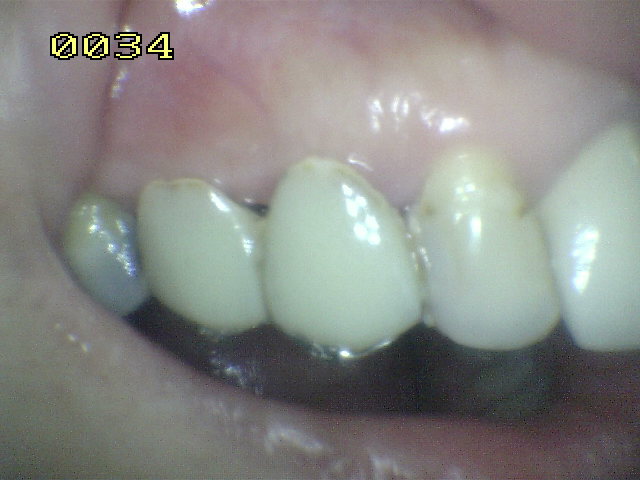

Puente Maryland en 24 en paciente de sexo masculino de 60 años de edad.

Observe la adaptación del metal al esmalte de este puente Maryland  que repone la pieza dental 24